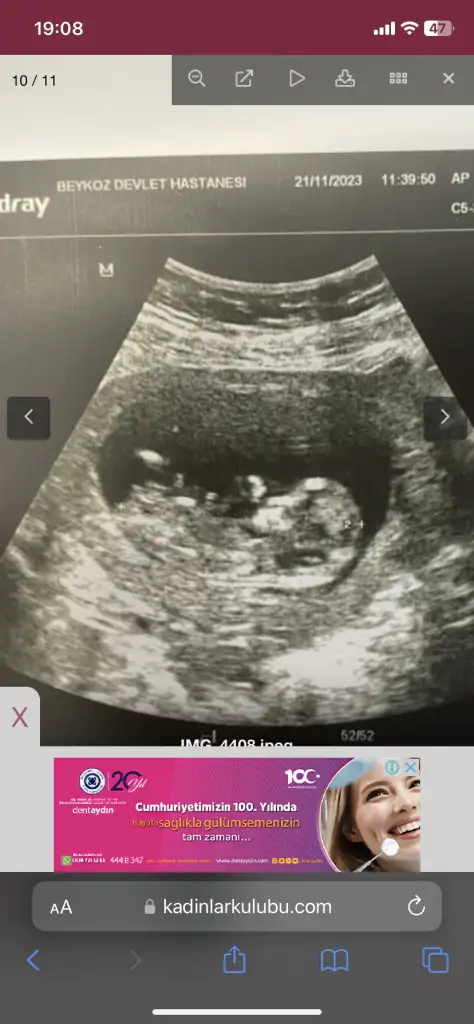

Benimkine de bakabilir misiniz doktorum 11+5te kız dedi 13+6da erkek dedi

İlk 3 fotoğraf 13+6

• IMG_4408.webp

IMG_4408.webp

40,6 KB · Görüntüleme: 119